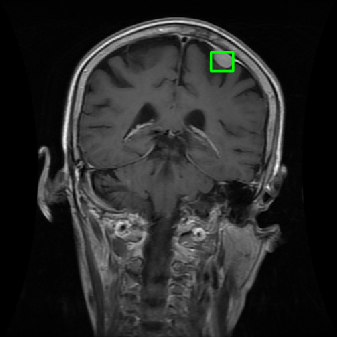

4.4 Comparison with cardic MR images for left ventricle segmentation

In this section, we continue to conduct experiments on cardiac MR images. However, we focus on the right ventricle, which is equally important as the left ventricle in cardiac MR diagnoses. In the near short-axis view, the left ventricle has a crescent shape, while the right ventricle is closer to circular. This does not imply that the right ventricle is easier to segment; in the MR images we use, the right ventricle often shows low-signal-intensity shadows, which may be caused by the imaging characteristics of certain tissues or fluids, leading to interference in segmentation. Moreover, there is a layer of myocardial tissue surrounding the right ventricle that overlaps with the boundary of the right ventricle, posing challenges for accurate identification.

Fig. 8 presents the segmentation results of the right ventricle from the DRLSE-ADMM [WALI2023109105], ABC model [WENG2021115633], RESLS [8765635], the RefLSM, and the ground truth. The results from the DRLSE-ADMM model in the 1st row reveal severe local minima due to low-signal-intensity shadows in the right ventricle. Additionally, both the ABC and RESLS models fail to correctly identify the right ventricle boundary because of the interference from surrounding myocardial tissue, as seen in the 1st and 3rd columns of Fig.8. In comparison, the proposed model gets more satisfactory segmentation results that are closer to the ground truth. Similarly, we evaluate the segmentation performance of all models by calculating the Dice and Precision values and drawing Fig. 9. This overlay plot presents the best, median and worst segmentation results, along with the overall range of outcomes that it is clear that the proposed model segments the right ventricle with greater accuracy than the other models and performs well in different images.